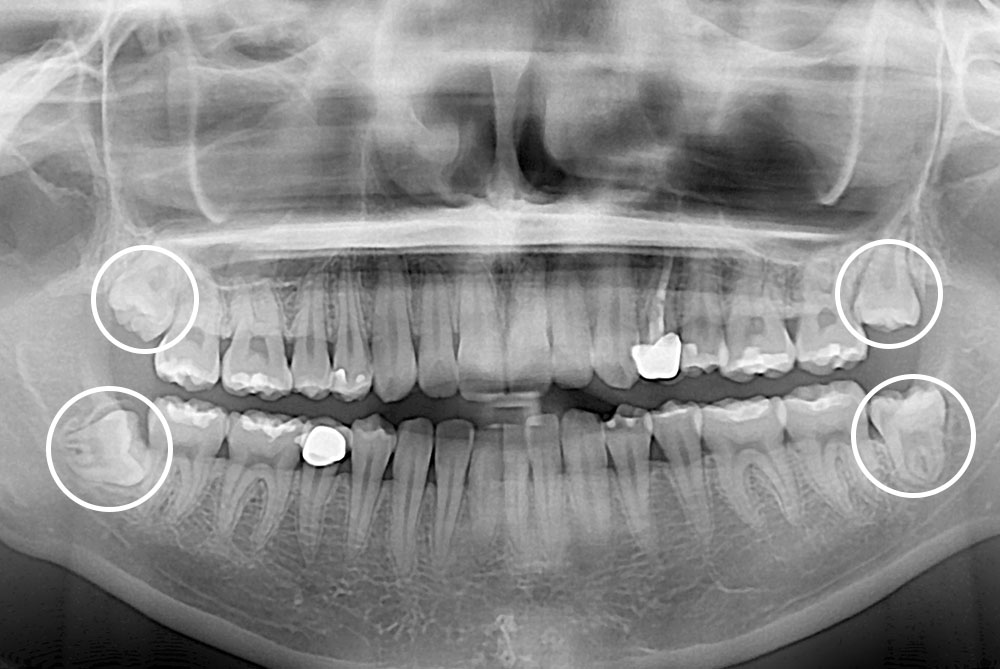

[사랑니] 매복 사랑니 발치

치료후 : 2022-05-19

세종치과는 구강악안면외과학 박사이신 원장님이 발치하는 치과입니다.